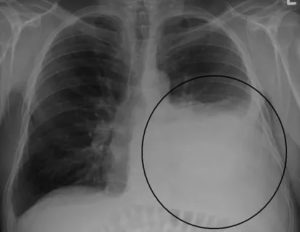

Плеврит возникает при накоплении избытка слизи и жидкости в полости плевры. Это частое явление после болезни и один из первых видимых признаков на стандартной рентгенографии грудной клетки.

Если жидкость распространится в легких, потребуется проведение плевроцентеза (плевральной пункции). При плевроцентезе в легкие вводят иглу и трубку для удаления избыточной жидкости. Затем применяют курс сильных антибиотиков.

- Плеврит – воспалительный экссудат образуется между плевральными листками.

- Эмпиема плевры – накопление гноя плевральных листках.